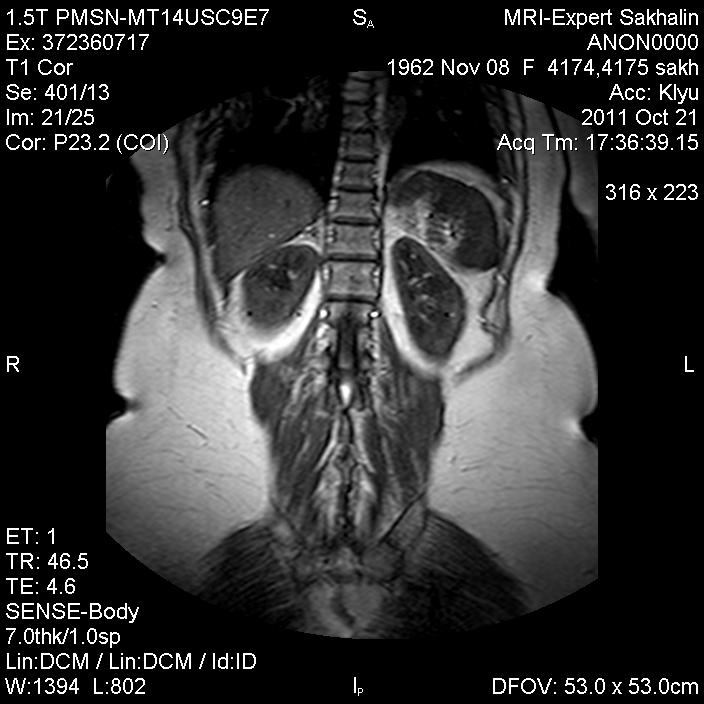

Образование надпочечника?

Женщина с подозрением на образование надпочечников.Лечащий врач  сбил ее с толку,сказав, что "ничего нести не нужно-сами разберутся".

Вижу образование только в правом надпочечнике.

Спасибо, Станислава, я тоже в правом  вижу.Написала,что предположительно аденома.

а вы прицельно надпочечники не делаете? в правом надпочечнике похоже на аденому

Возможно макронодулярная гиперплазия. Аденома должна на жироподавлении давиться хоть немного (по данным Видара).

Евгений Второй-не знала, но почитаю еще раз про аденомы.Возможно и гиперплазия-я сама долго колебалась между ними.

Все аденомы содержат жир в большем или меньшем количестве... Чаще всего - в очень достаточном количестве, чтобы МРТ-картина существенно изменилась при жироподавлении.